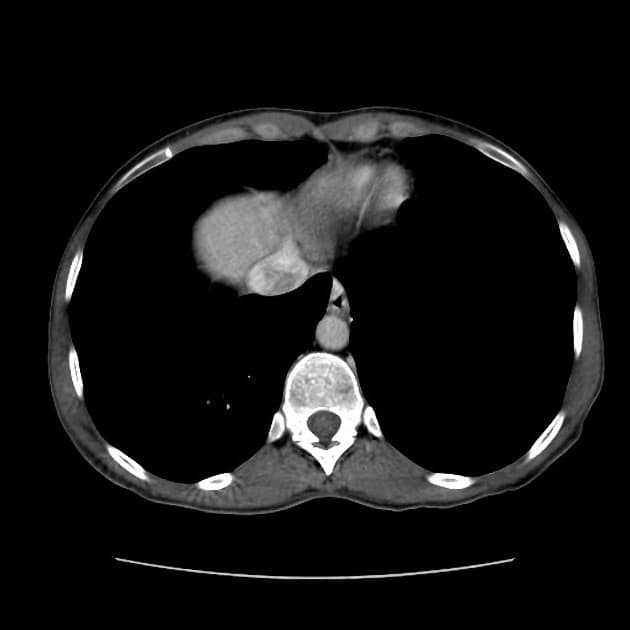

Chụp cộng hưởng từ ổ bụng (abdominal MRI)

- Tổn thương dạng thùy (lobulated) ở thuỳ gan phải, chủ yếu tại các phân đoạn 7 và 8.

- Tổn thương có những vùng tăng tín hiệu (hyperintense) nhẹ so với nhu mô gan trên hình ảnh T1 trước tiêm thuốc, phù hợp với xuất huyết (hemorrhage).

- Không thấy mỡ nội tại (gross lipid content) trong tổn thương.

- Ghi nhận tình trạng steatosis gan lan tỏa nhẹ (mild diffuse hepatic steatosis).

- Không có hình ảnh hình thái học của xơ gan (cirrhosis).

- Không thấy máu trong ổ bụng (hemoperitoneum).

Chuỗi hình ảnh động trước và sau tiêm thuốc (Pre & postcontrast dynamic sequences)

- Khối tổn thương tăng quang ở thì động mạch, dạng thùy, tại thuỳ gan phải, chủ yếu ở các phân đoạn 8 và 7.

- Tín hiệu của khối giảm xuống mức nền trên các thì trễ (fades to background signal intensity on delayed sequences).

- Không thấy hiện tượng washout.

- Không thấy hình thành giả màng bao (pseudocapsule formation).

Bệnh nhân đã được thực hiện cắt bỏ gan phải (right hepatectomy): chẩn đoán bệnh lý là u tuyến gan (hepatic adenoma), phù hợp với hình ảnh MRI.

U tuyến gan (hepatic adenoma) – phức tạp do xuất huyết (complicated by hemorrhage)

U tuyến gan là một khối u lành tính ở gan, thường gặp ở người trẻ tuổi, đặc biệt là phụ nữ sử dụng thuốc tránh thai đường uống. Khối u có thể gây đau bụng cấp tính do xuất huyết trong khối u như trường hợp này. Trên cộng hưởng từ, u tuyến gan thường hiện diện như khối u dạng thùy, tăng quang mạnh ở thì động mạch, không có hiện tượng washout hay hình thành giả màng bao – giúp phân biệt với ung thư biểu mô tế bào gan. Tín hiệu tăng trên T1 do xuất huyết và không chứa mỡ là các đặc điểm hình ảnh quan trọng. Điều trị bao gồm cắt bỏ phẫu thuật đối với các u lớn (>5 cm) hoặc có biến chứng như xuất huyết để ngăn ngừa vỡ và chuyển ác.